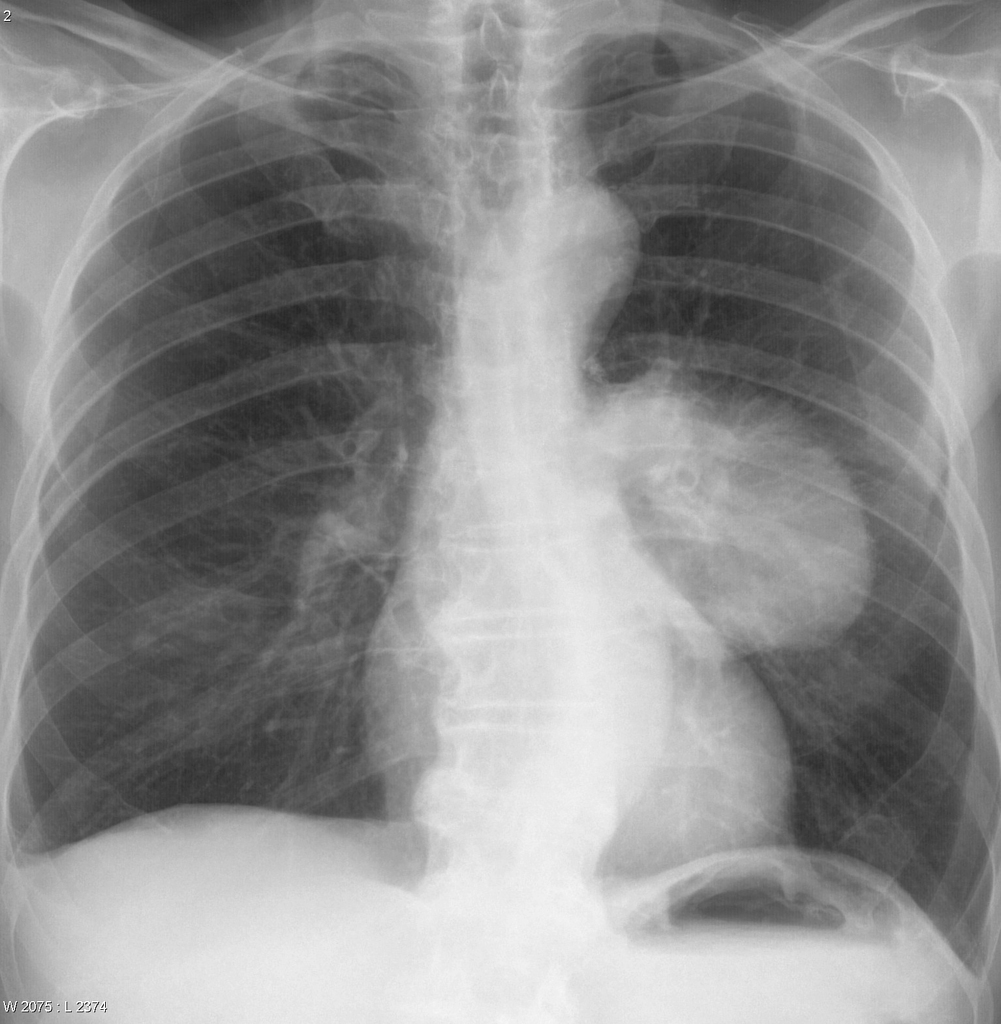

What does loss of definition of left heart border indicate?

Lingular consolidation

What does a loss of definition of aortic knuckle indicate?

Aneurysm